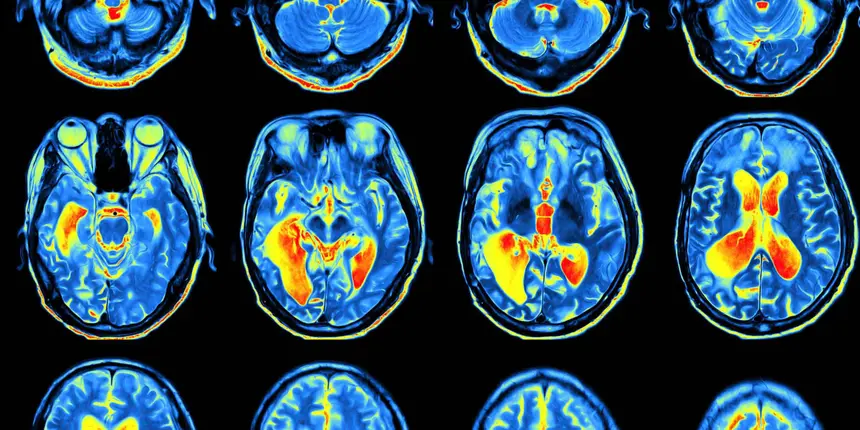

При помощи функциональной магнитно-резонансной томографии (фМРТ) мозга была выявлена более активная область, когда участники сообщали, что видели какой-то рисунок. Эта веретенообразная извилина находится в районе висков. Она активируется как при виде чего-то в реальности, так и при представлении этого. Интересно, что эта активация предсказывает, считаем ли мы что-либо реальным. Далее этот сигнал оценивается передней островковой долей. Активность выше определённого порога воспринимается как реальная, а активность ниже — как воображаемая.